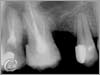

Endodontia (root treatment)